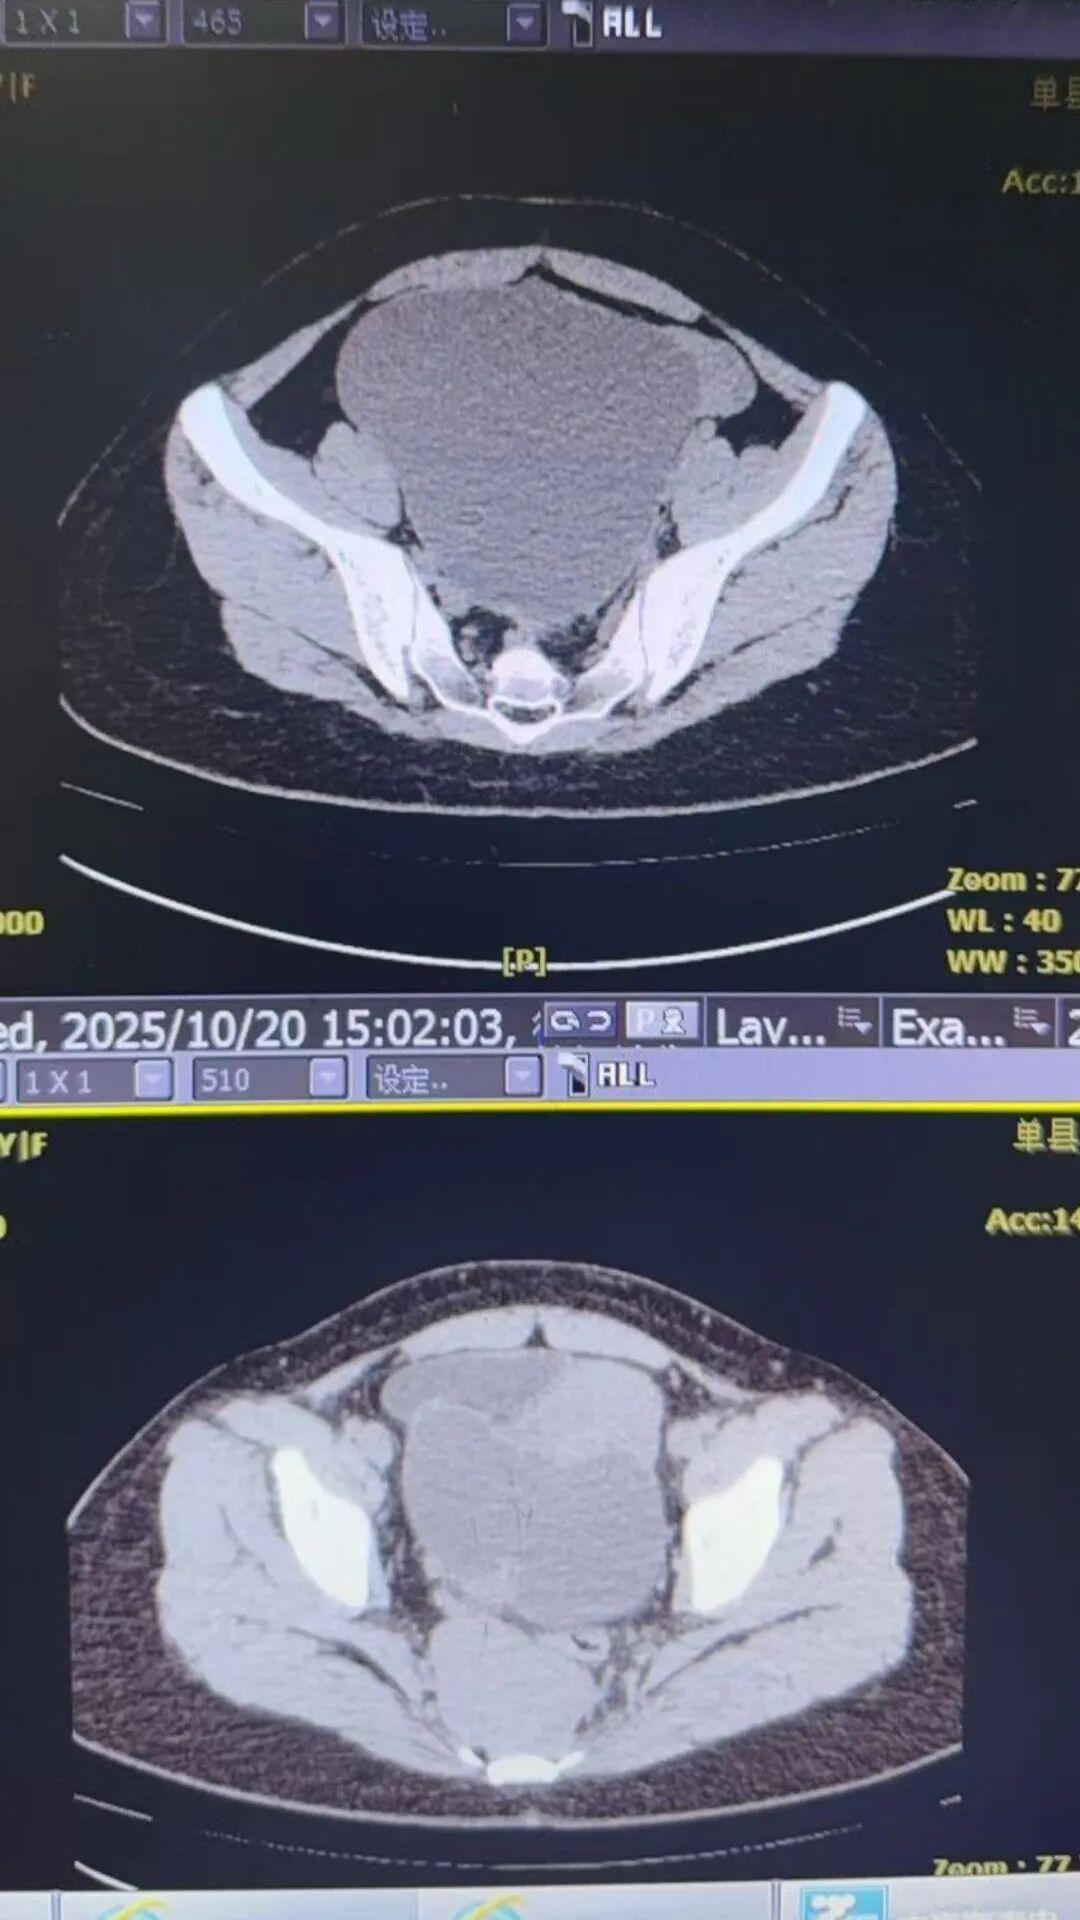

患者因“查体发现盆腔包块1天”入院,患者在出生仅40余天就因“骶尾部肿瘤”接受手术治疗,但当时未能完整切除病灶。此后多年间,患者于外院先后经历了盆腔肿瘤手术、后穹隆穿刺手术等多次治疗,盆腔内形成了重度粘连,使得解剖结构异常复杂。此次检查发现,患者盆腔内存在一个大小约20×18×16cm的巨大肿瘤,活动度极差。在直肠后方、骶骨前方还触及一个约7×6×5cm的质硬肿瘤,肿瘤紧贴骶骨,位置固定,活动度差,给手术带来了巨大挑战。骶前区域因其位置深、解剖结构复杂、毗邻重要血管神经,一直被妇科医生视为“手术禁区”。